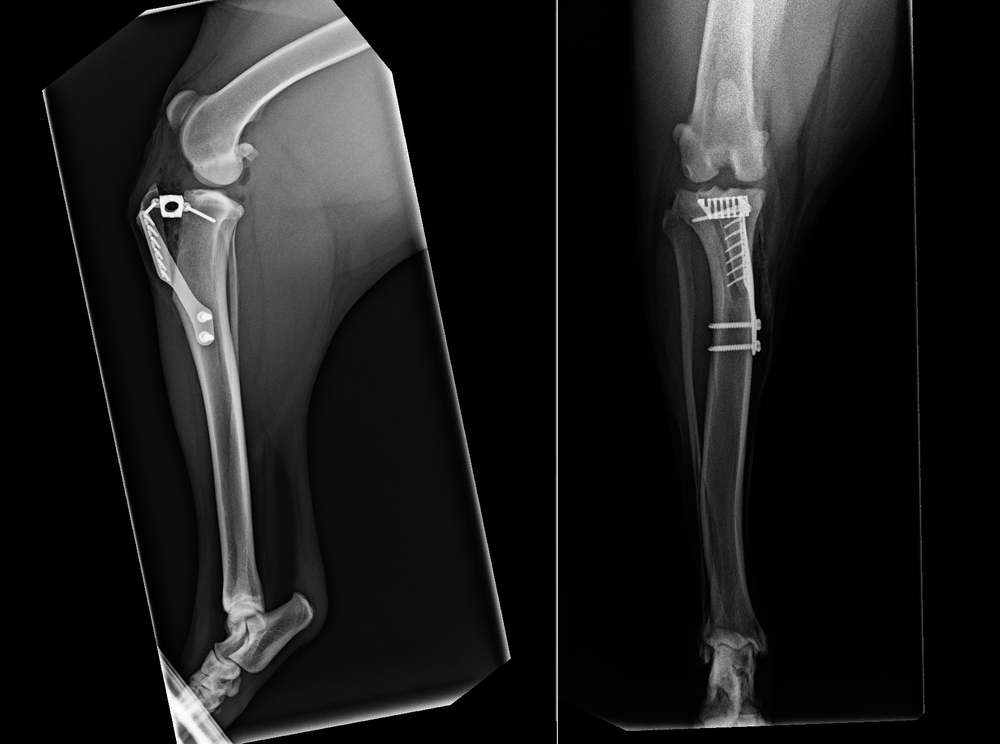

This surgery to remove the cage that is encased in bone is invasive and difficult The TPLO, on the other hand, doesn't have a cage and only has a plate and screws, which can easily be removed because the bone doesn't grow into them TTA radiographs showing cage, fork plate/screws TTA radiographs showing cage, fork plate/screwsDr Khuly goes on to describe TPLO as 'the gold standard' for dog knee surgery "TPLO or TTA, or another of the socalled, "leveling osteotomies" These procedures are currently considered the "gold standard" approach to surgical management of the cruciate ligament injuryaffected patient who weighs over 25 pounds It's normal to see a dog limping after ACL surgery, especially in the first few days after surgery While recovery times vary from dog to dog, it can take six to eight weeks for your dog to be back to normal after knee surgery

TTA Postop Note the 90 degree angle through the knee jointTibial Tuberosity Advancement (TTA) SURGERY for ACL CORRECTION The most common knee injury in the dog is rupture of the Cranial Cruciate Ligament (CCL), also frequently referred to as the Anterior Cruciate Ligament (ACL) What is a dog ACL surgery?